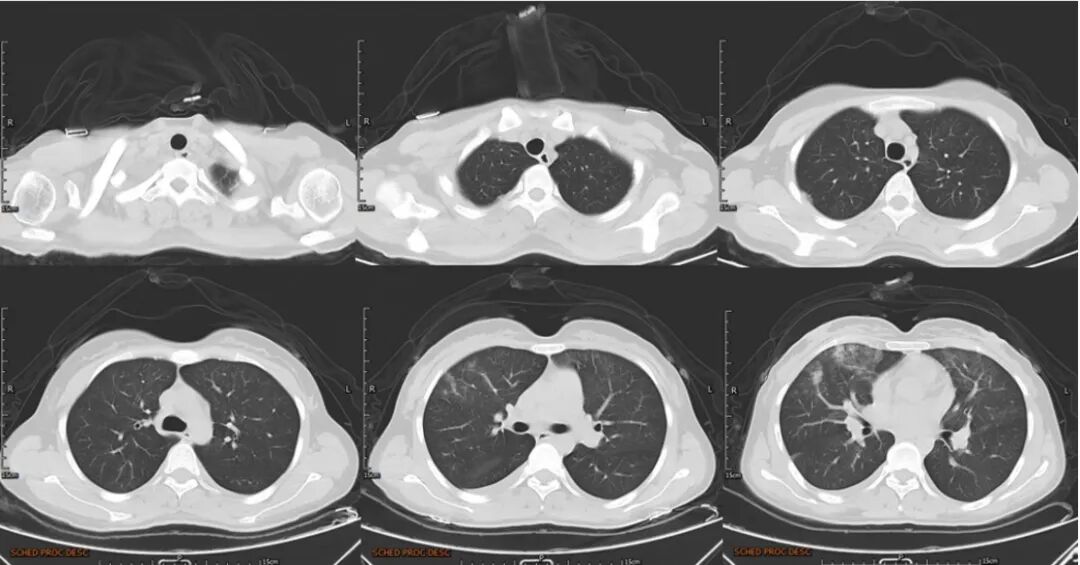

29岁女性,2021年2月入院。间断发热3个月,进行性呼吸困难23天。患者3个月前(2020年12月)出现间断发热,傍晚发热为主,Tmax 38.5℃,伴轻微咳嗽,查胸部CT未见明显异常,口服中成药治疗,仍有间断发热。1月余前再次因发热就诊于当地医院,复查CT示“双肺多发小结节,考虑纤维灶可能”,查血WBC、N%、CRP、ESR升高,予以咳嗽糖浆治疗,仍发热。

3周前患者再次发热,伴剧烈咳嗽、咯血痰,量不多,伴明显呼吸困难,再次就诊于当地医院急诊,查CT提示“双肺炎性病变,右侧胸腔积液,左侧胸膜渗液,双肺多发小结节”,血常规提示WBC 14.04×109/L,NEUT 12.4×109/L,CRP 21.58 mg/L;鼻导管吸氧10 L/min时指尖氧饱和度波动于70%左右,诊断“重症肺炎,右侧胸腔积液”收入ICU。

患者胸部CT示双肺上叶及中下叶均有磨玻璃影,部分呈腺泡结节,融合成片。

图片